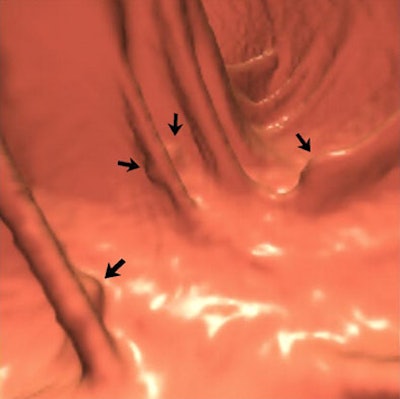

"Multiple polypoid lesions measuring up to 9 mm and located within matching colonic segments were confirmed at optical colonoscopy performed several hours after CT colonography," Andrews et al wrote. "The lesions, however, were not mucosal polyps, but instead were well-defined raised submucosal vascular blebs with a distinctive bluish hue. Biopsy was not performed because of the vascular nature of the lesions, combined with the fact that the endoscopic appearance was characteristic and diagnostic."

| A 64-year-old man was referred for initial colorectal screening. Endoluminal 3D (above and below) and coronal 2D (bottom) images from screening CT colonography showed multiple subcentimeter polypoid lesion (arrows). Images below and bottom show the same lesion on 3D and 2D, respectively. Lesions were all of soft-tissue attenuation and measured up to 9 mm. Images reprinted with permission of the American Roentgen Ray Society (ARRS) from Lee et al, AJR 2006; 186:1113-1115. |